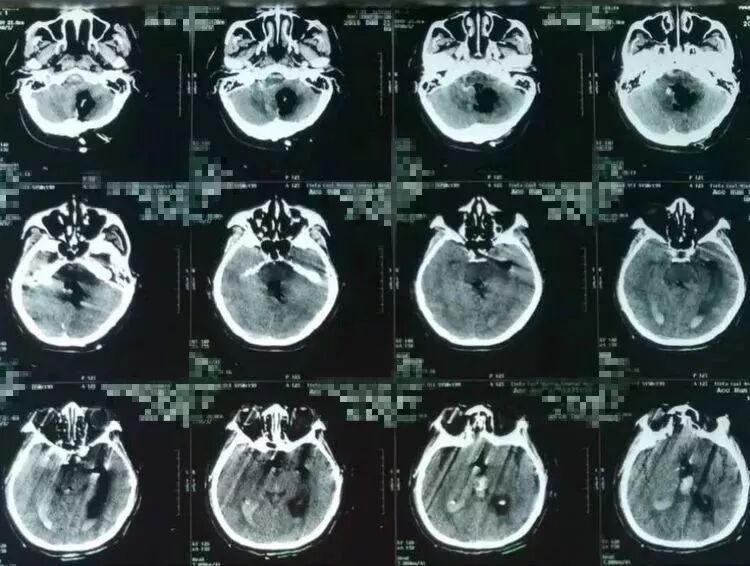

突发意识障碍3小时,既往有高血压病史数年。入院后病人自主呼吸,GCS=6,瞳孔正常。CT提示右侧小脑半球深部脑内血肿,破入IV脑室和III脑室。

术后病人生命指征稳定,瞳孔正常,自主呼吸正常,意识障碍较术前改善。复查头CT可见小脑内、IV脑室和III脑室内血肿清除满意。